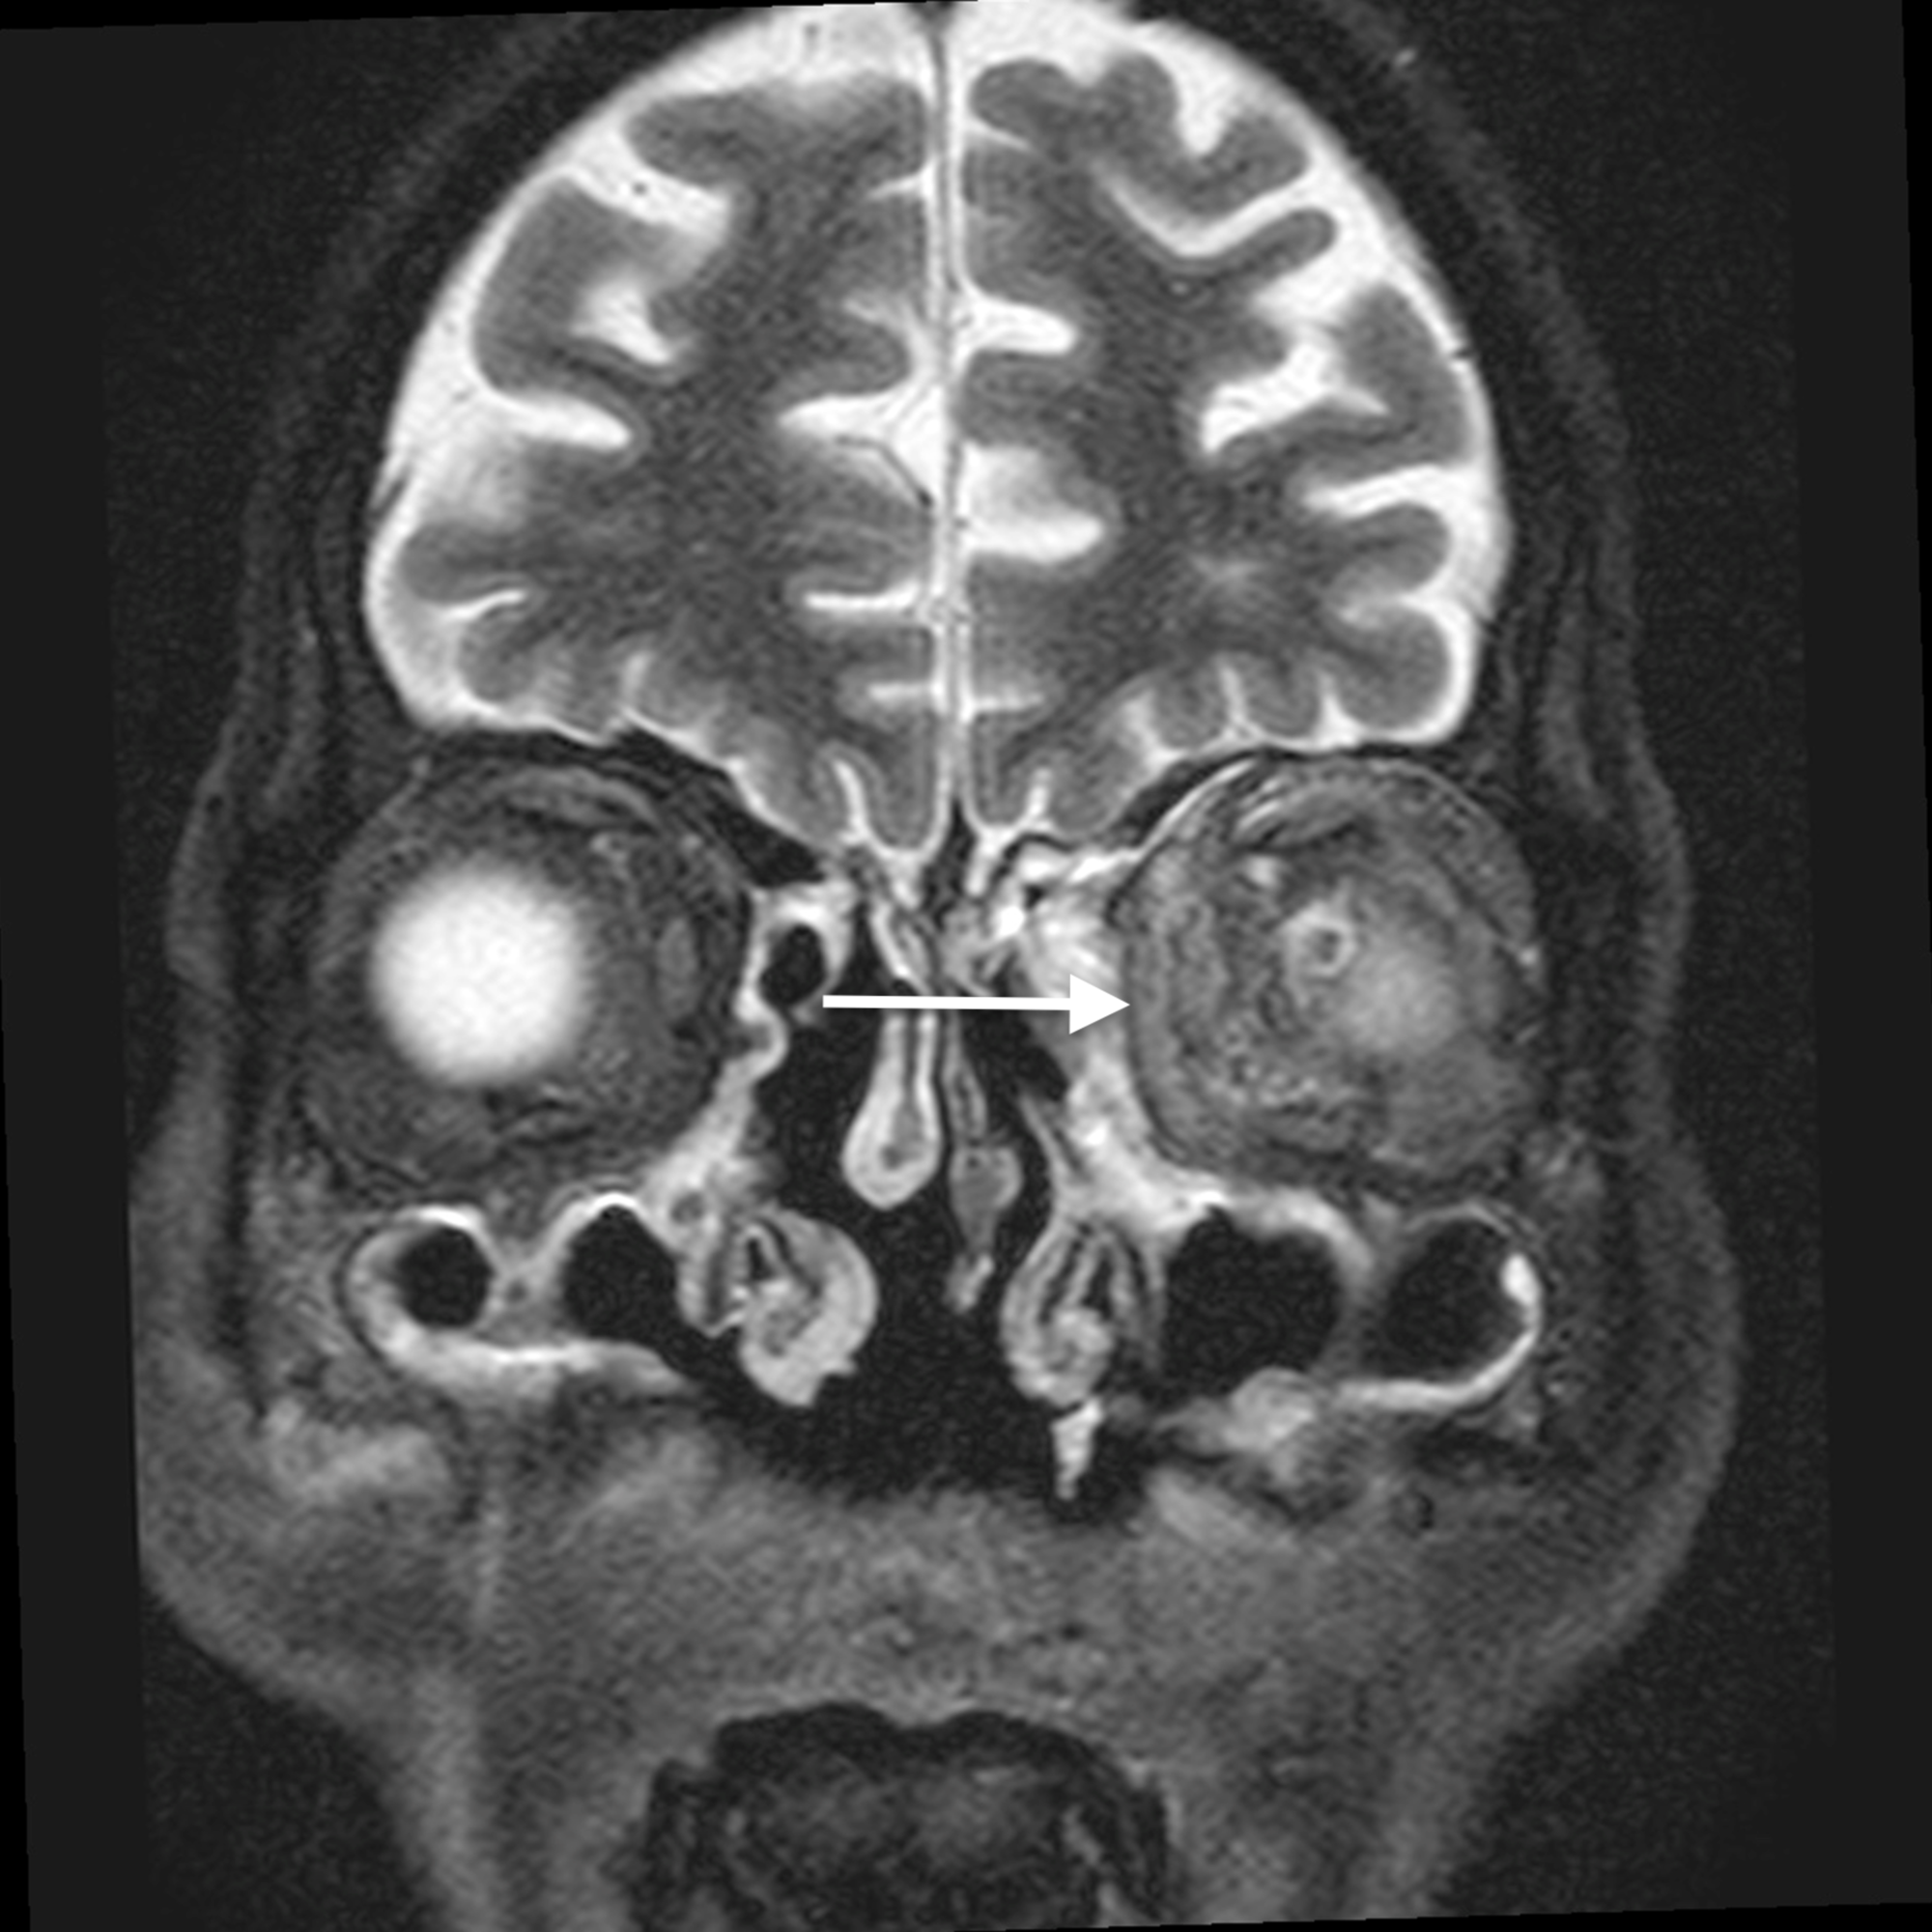

Twelve cases (80%) showed involvement of multiple paranasal sinuses and amongst the cases associated with sinusitis, the commonest inflamed paranasal sinus was found to be the ethmoid sinus (twelve cases), followed by the frontal sinus (four cases). None of the sinuses were involved in two cases, whereas one case (6.6%) showed the involvement of single (ethmoid) sinus.

Amongst the fifteen cases of orbital/periorbital cellulitis, there were only two cases of isolated preseptal cellulitis (13.33%), five cases of postseptal cellulitis (33.33%) and eight cases of both preseptal and postseptal orbital cellulitis (53.33%).

The main complications of orbital cellulitis (Figures 2-4) encountered in our study were:

The most common predisposing factor for orbital cellulitis is paranasal sinus disease [11]. The most common cause of orbital cellulitis in our study was found to be ethmoid sinusitis, followed by frontal sinusitis. This was concordant with the study done by Chaudhry et al. [12]. However, the disease may also result from infectious processes of the face or pharynx or foreign bodies, or it may develop secondary to trauma or septicemia. Orbital infections arising from secondary to dental infections are rare [13].

The factor primarily responsible for the development of orbital cellulitis in ethmoid sinusitis is the anatomic contiguity of the two structures, thin lamina papyracea and the valveless ethmoidal veins, which allow rapid spread of infection into the orbit [14]. Apart from being thin, the lamina papyracea has multiple tiny natural deficiencies, perforating nerve vessels [15]. Another common method of spread of infection is by means of interference with the venous drainage of orbital contents. Infection from the nasal cavity and paranasal sinuses may also spread by means of myriad direct connections of the veins of these structures with the veins of orbit and cavernous sinuses [14]. In the absence of drainage, an orbital abscess carries a high risk of intracranial spread and visual impairment [16-17]. Thus, it is imperative to drain an orbital or subperiosteal abscess without any delay. In addition, without drainage of the abscess, the antibacterial potency of the antibiotics is reduced because of inadequate enzymatic degradation of the bacteria in the purulent milieu [18].